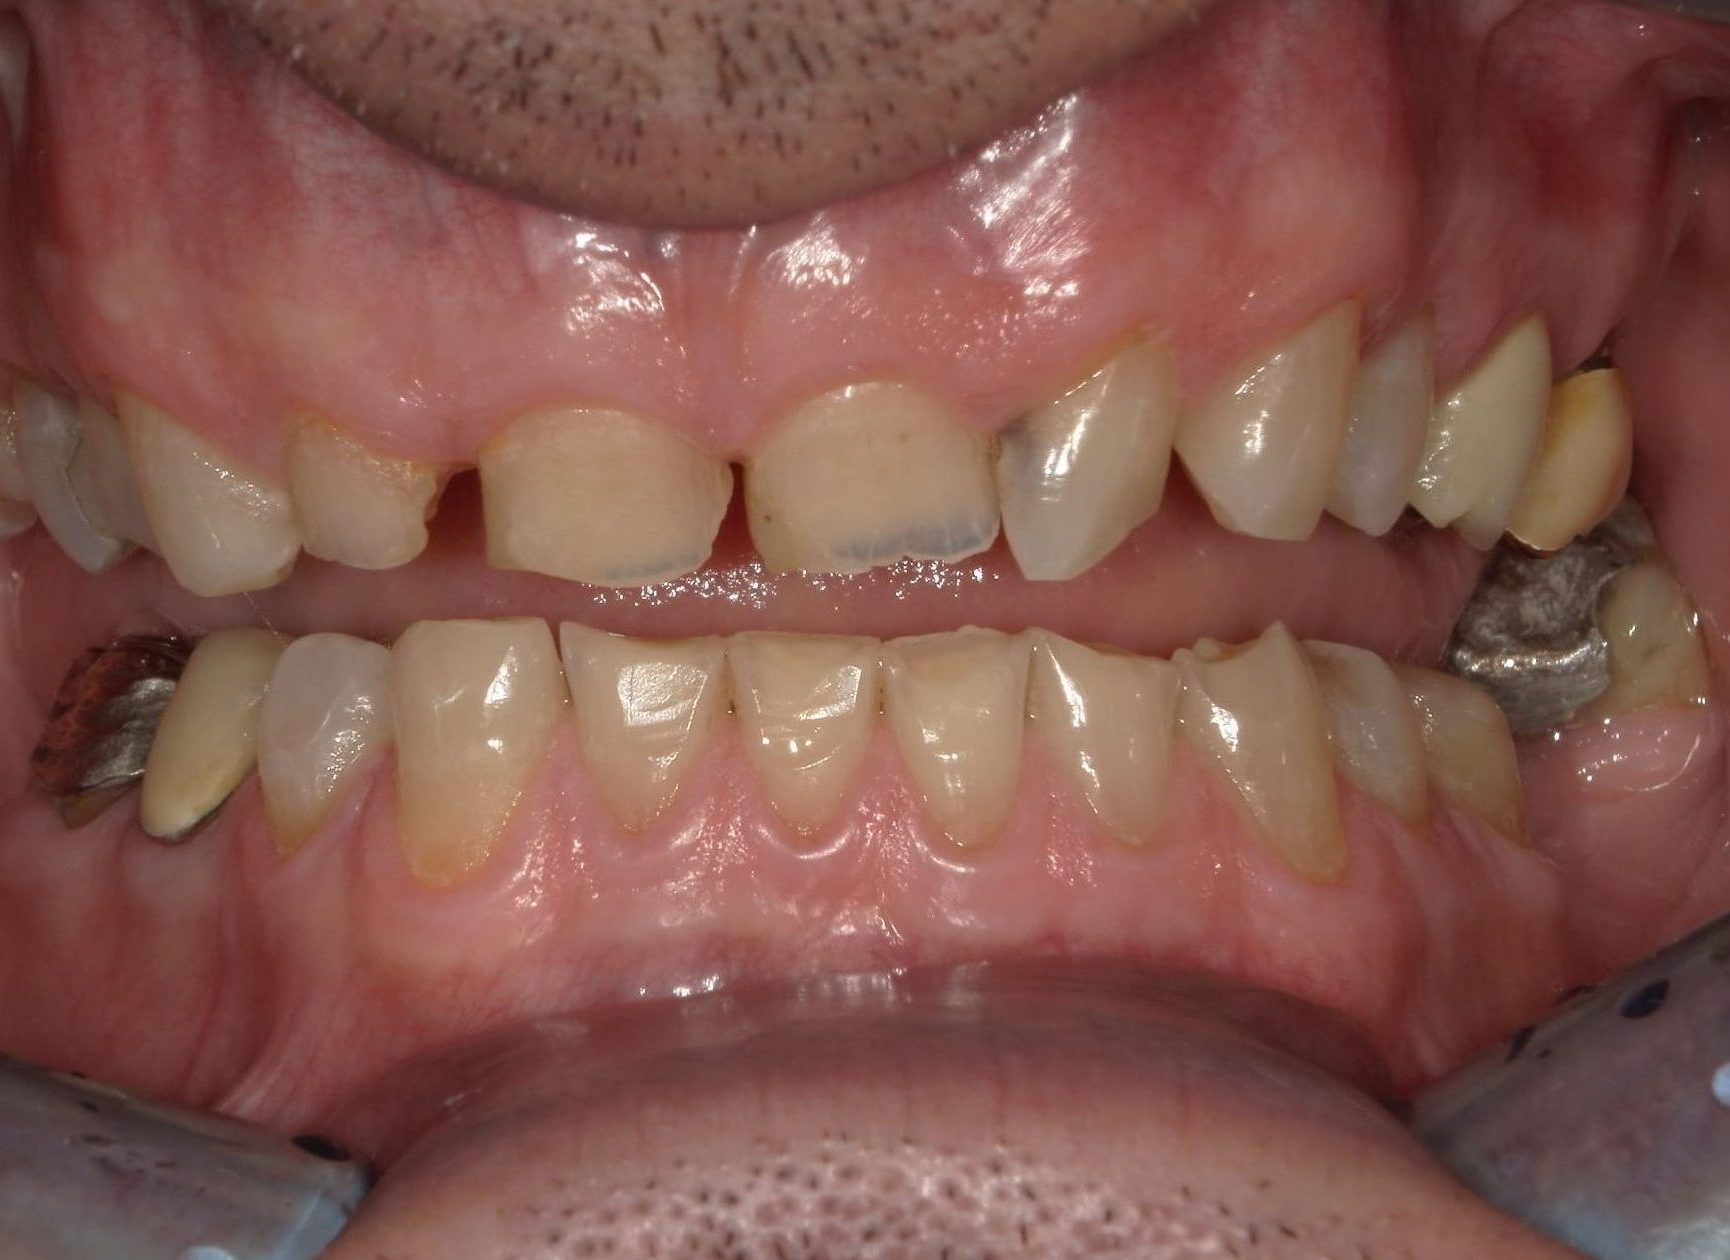

Prima

Dopo